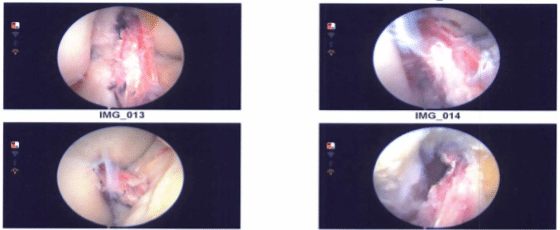

The medial meniscus had a bucket handle rupture that was dangling in the intercondylar notch. A medial anterior portal was created, and the bucket handle rip was successfully reduced. It was decided to repair it from the inside out. To prepare the margins, a meniscus grasper was used.

Arthrex meniscal sutures were utilized three times to mend horizontal mattress sutures, and the repair was successful. Photographs were taken and preserved. The ACL was prioritized, and the medial surface of the lateral femoral condyle was prepared for ACL surgery.

The tibial plateau was similarly treated and marked with the ArthroCare wand. Another arthroscope was placed through the medial portal, followed by the insertion of a femoral jig and the insertion of a sleeve.

The knee was then cycled 30 times in flexion and extension, the ligament was tightened on both sides, and the sutures were knotted together and snipped. The final images were stored and saved.

Acromioplasty was performed to eliminate an impingement on the lateral femoral condyle. As a result, there was no impingement. The final photographs were shot and preserved. The wound was irrigated and drained carefully.

Intraoperative images